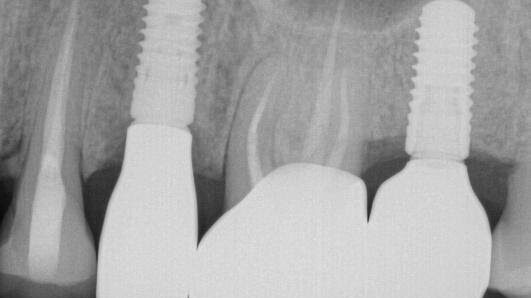

Iatrogenic Screw Retrieval of a Poorly Placed TSV Implant, Creating a Type VI Screw Recovery Case – 0040

This implant case showcases an example of an Iatrogenic screw retrieval of a poorly placed TSV implant, Creating a Type VI Screw Recovery Case.